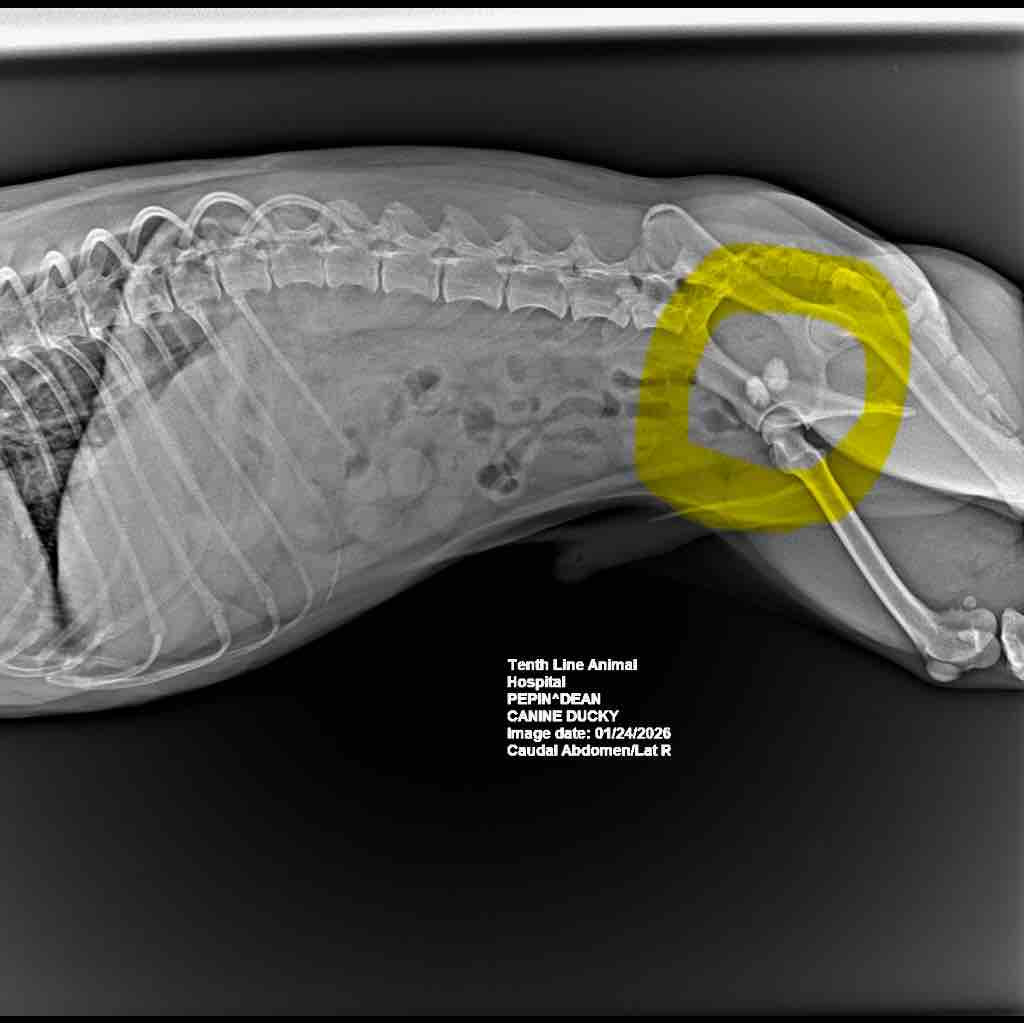

Ducky has two giant kidney stones that are not dissolvable and require life-saving surgery ASAP. He has had all needed pre-examinations, X-rays etc. and currently has temporary pain-relieving medication (already totalling over $1000). The medication can help with pain for the next 2-3 weeks but he requires the surgery ASAP. The surgery alone is around $4000 (plus meds and post-op costs) and as a single father it just isn’t doable on my own. Im not one to typically ask for help, but Ducky has always been there for me so I’m reaching out as far as I can to give Ducky a fighting chance that he so deserves.